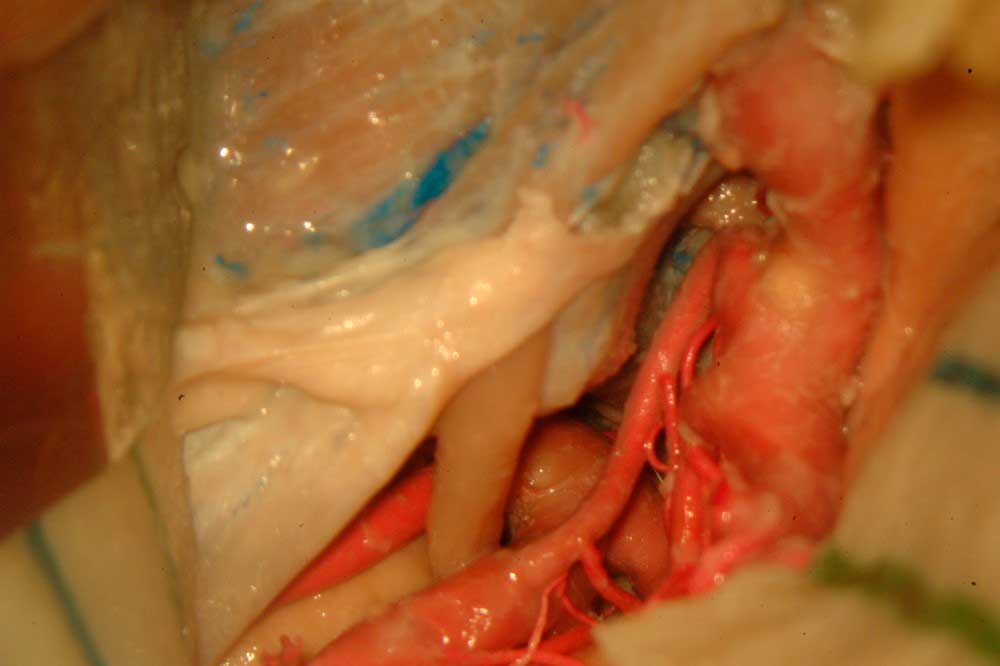

Anatomia Microcirúrgica e abordagens ao seio cavernoso – um estudo tridimensional estereoscópico com correlação clínicoradiológica

O seio cavernoso é uma das regiões mais complexas do corpo humano e pode ser acometido por diversas patologias. Atualmente, diversos tipos de tratamentos podem ser usados para tratar doenças nesta região, porém, o conhecimento anatômico ainda é fundamental para estabelecer o melhor manejo. Nosso objetivo é apresentar a anatomia microcirúrgica do seio cavernoso, as abordagens cirúrgicas (incluindo a abordagem endonasal endoscópica), a correlação radiológica desta anatomia, bem como uma série inicial de casos. As fotos são apresentadas pelo método convencional e anaglífico estereoscópico. São descritas as estruturas neurovasculares do seio cavernoso bem como suas relações ósseas e durais, as paredes e os triângulos da base do crânio relacionados ao seio cavernoso. As abordagens crânio-órbito zigomática, transpetrosa, zigomática e endonasal endoscópica são apresentadas, sendo as estruturas anatômicas identificadas também nos exames de imagem. Casos ilustrativos de neurinomas, schwanomas e meningeomas ilustram esta anatomia.